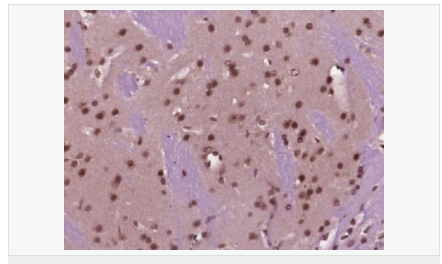

產(chǎn)品應用WB=1:500-2000 ELISA=1:5000-10000 IHC-P=1:100-500 IHC-F=1:100-500 Flow-Cyt=1ug/test ICC=1:100 IF=1:100-500 (石蠟切片需做抗原修復)

細胞定位細胞核 細胞漿